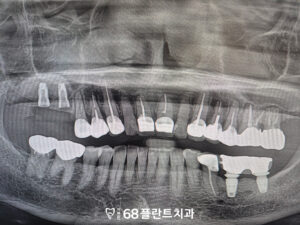

◆ 전 > 후 ◆

이렇게 수술이 마무리 된 후

환자분께서는 많이 아플까봐 걱정하셨는데,

생각보다 아프지도 않고

괜찮다며 만족해주셨습니다.

주의사항을 잘 지켜주시고

관리를 잘 해주셔서

특별한 염증 없이 치유가 잘 되고 있는것을

확인할 수 있었습니다.